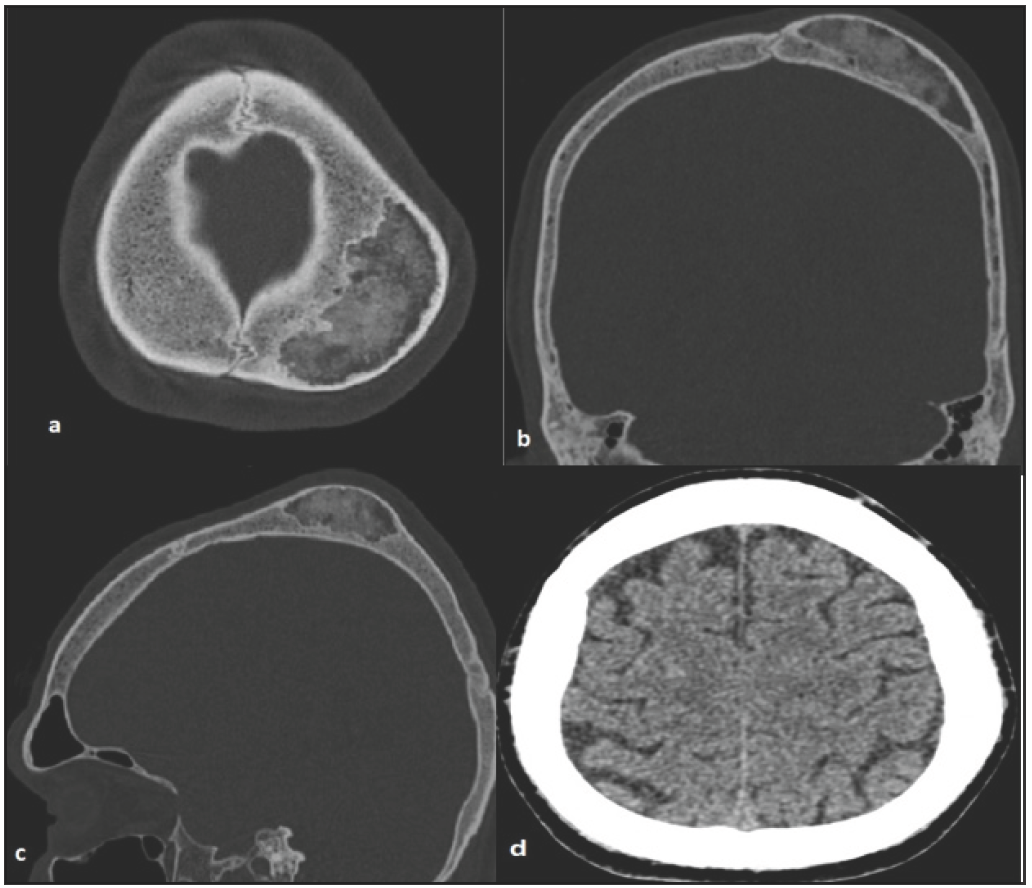

Plain CT brain scan showed a solitary, well-defined, expansile lytic lesion in the left parietal bone measuring 4.7 × 2.3 cm [Figure 1]. There was no intracranial extension of the lesion. The outer and inner cortices were intact. Further imaging with contrast CT could not be performed as the patient’s renal function test was abnormal. The differential diagnoses in this case include Brown’s tumor (in the background of chronic kidney disease [CKD]), hemangioma, and less likely malignancy.

- (a-c) CT brain axial, coronal, sagittal bone window shows a well defined osteolytic lesion with mixed matrix. Thinning of outer cortex noted. No inner cortex breech noted. (d) CT brain scan axial soft tissue window shows no parenchymal extension. CT: Computed tomography.